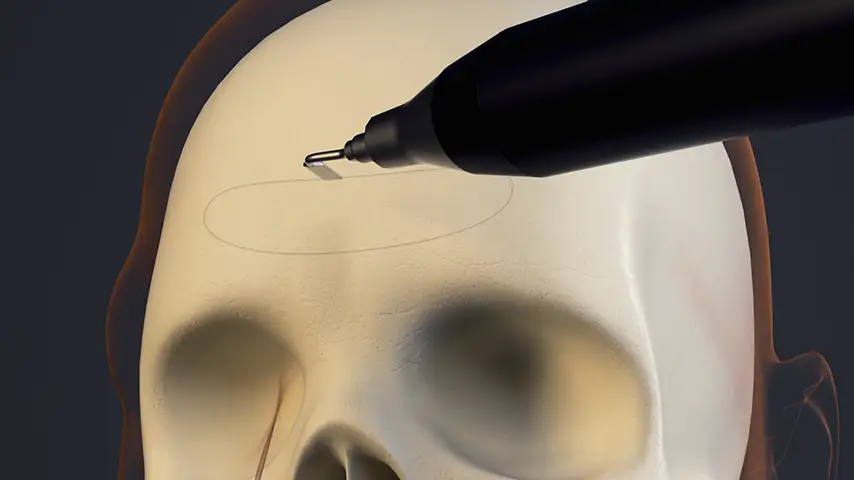

Frontal sinus opening – external approach

Selective osteotomies, safety on soft tissues

Advantages over traditional tools

Reduced risk of damaging anatomically complex regions

Greater intraoperative control and bone management

Micrometric cut for minimal bone loss

Reduced heat generation to avoid bone necrosis